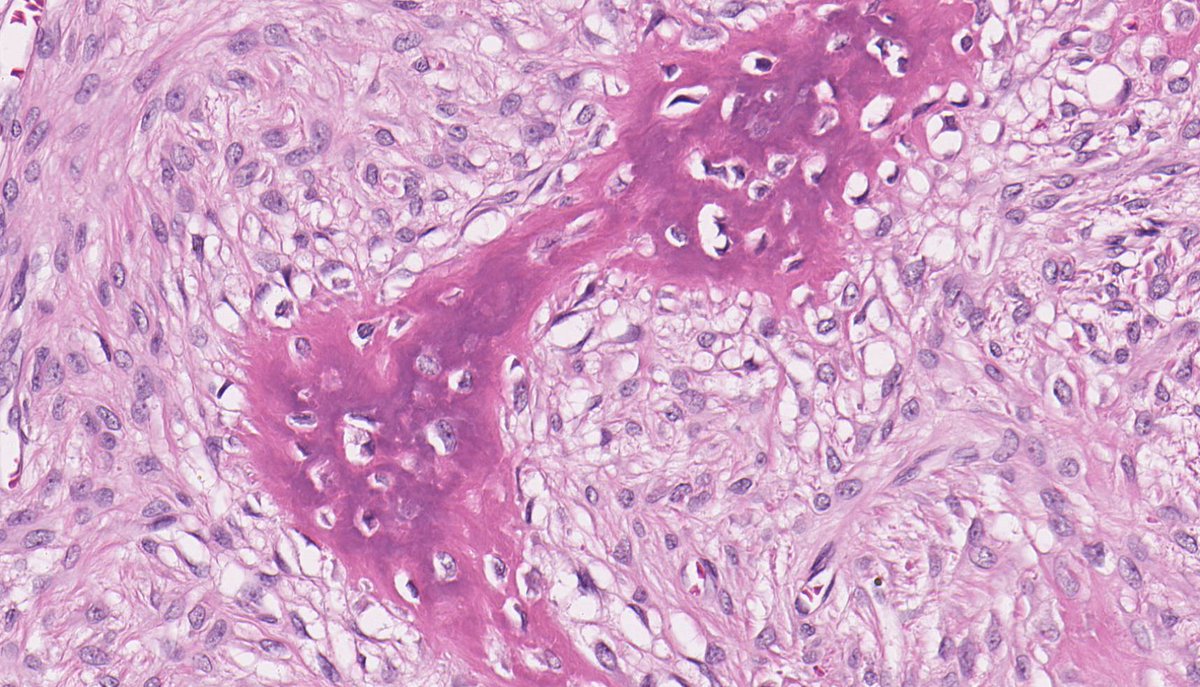

NUT Carcinoma. Undifferentiated tumor cells with areas of abrupt keratinization. Nuclear expression of NUT with a speckled pattern. NGS: NSD3::NUTM1 #ENTpath

NUT Carcinoma. Undifferentiated tumor cells with areas of abrupt keratinization. Nuclear expression of NUT with a speckled pattern. NGS: NSD3::NUTM1

#ENTpath